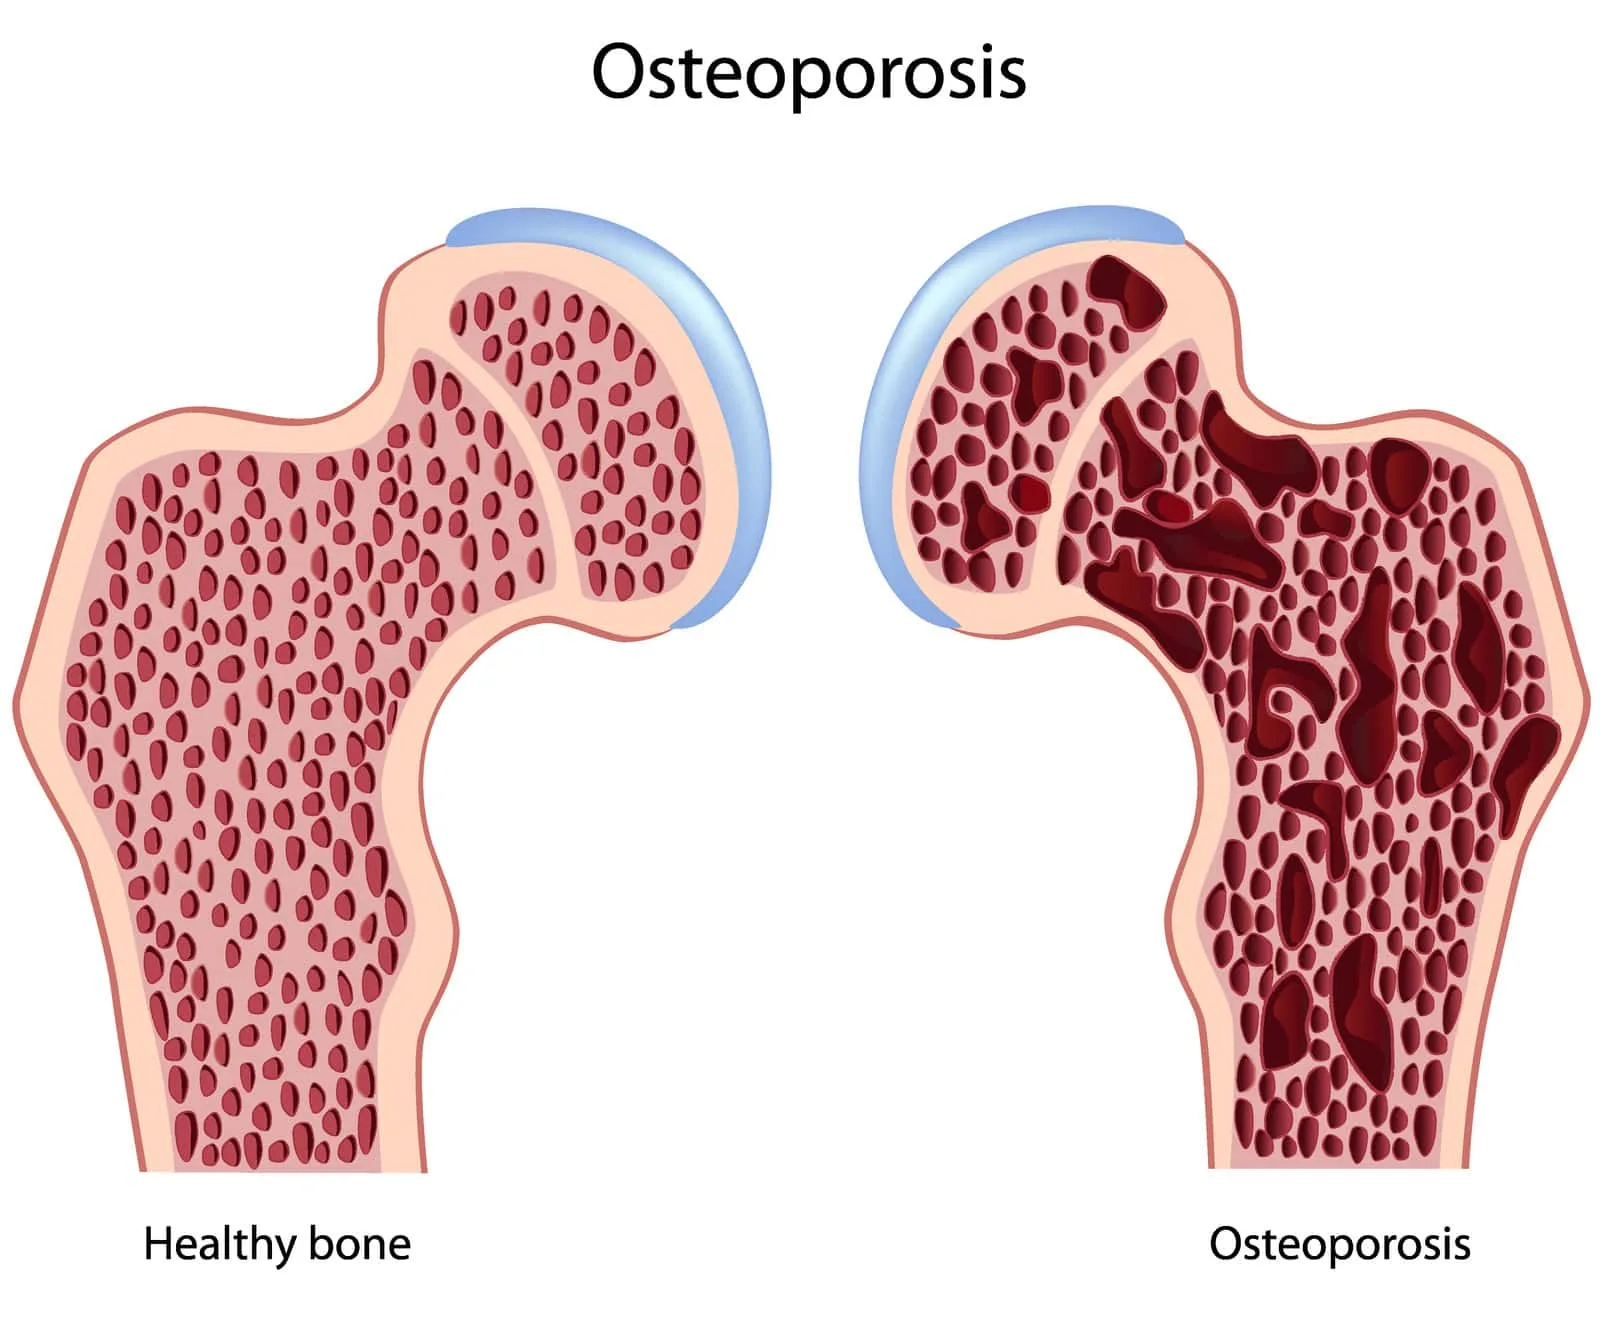

(فیزیوتراپی پوکی استخوان) پوکی استخوان یا استئوپروز بیماری است که موجب کاهش تراکم مواد معدنی استخوان و یا افزایش شکنندگی استخوان می شود. این شرایط می تواند باعث ضعف و شکننده شدن استخوانها شود. در صورتی که به پوکی استخوان مبتلا شده اید، ریسک ایجاد شکستگی و ترک خوردگی استخوان به خصوص در نواحی ستون فقرات، لگن، و مچ دست شما بطور مشخص افزایش پیدا می کند.

با افزایش سن بافت استخوانی به سرعت از بین می رود. شیوع پوکی استخوان در زنان مسن بیشتر می باشد. قطع عملکرد تخمدان ها در زنان یائسه (بعد از ۵۰ سالگی) باعث از بین رفتن سریع تراکم استخوانی می شود. به هر حال، آسیب ناشی از پوکی استخوان سال ها قبل از این شرایط آغاز می شود. به خاطر اینکه حداکثر سطح تراکم استخوانی در حدود سن ۲۵ سالگی به دست می آید، مهم است که در این سنین استخوان های قوی در افراد ایجاد شود تا به این ترتیب استخوان ها برای بقیه سال های زندگی قوی باقی بمانند. در این شرایط مصرف کافی مواد غذایی حاوی کلسیم می تواند یک بخش اصلی در تشکیل استخوان های قوی باشد.

در پوکی استخوان، بازسازی استخوان تحت تاثیر عوامل مختلف داخلی، خارجب و سن قرار دارد. پوکی استخوان زمانی ایجاد می شود که بین فرآیند تشکیل استخوان جدید و جذب استخوان قدیمی تعادل وجود نداشته باشد.